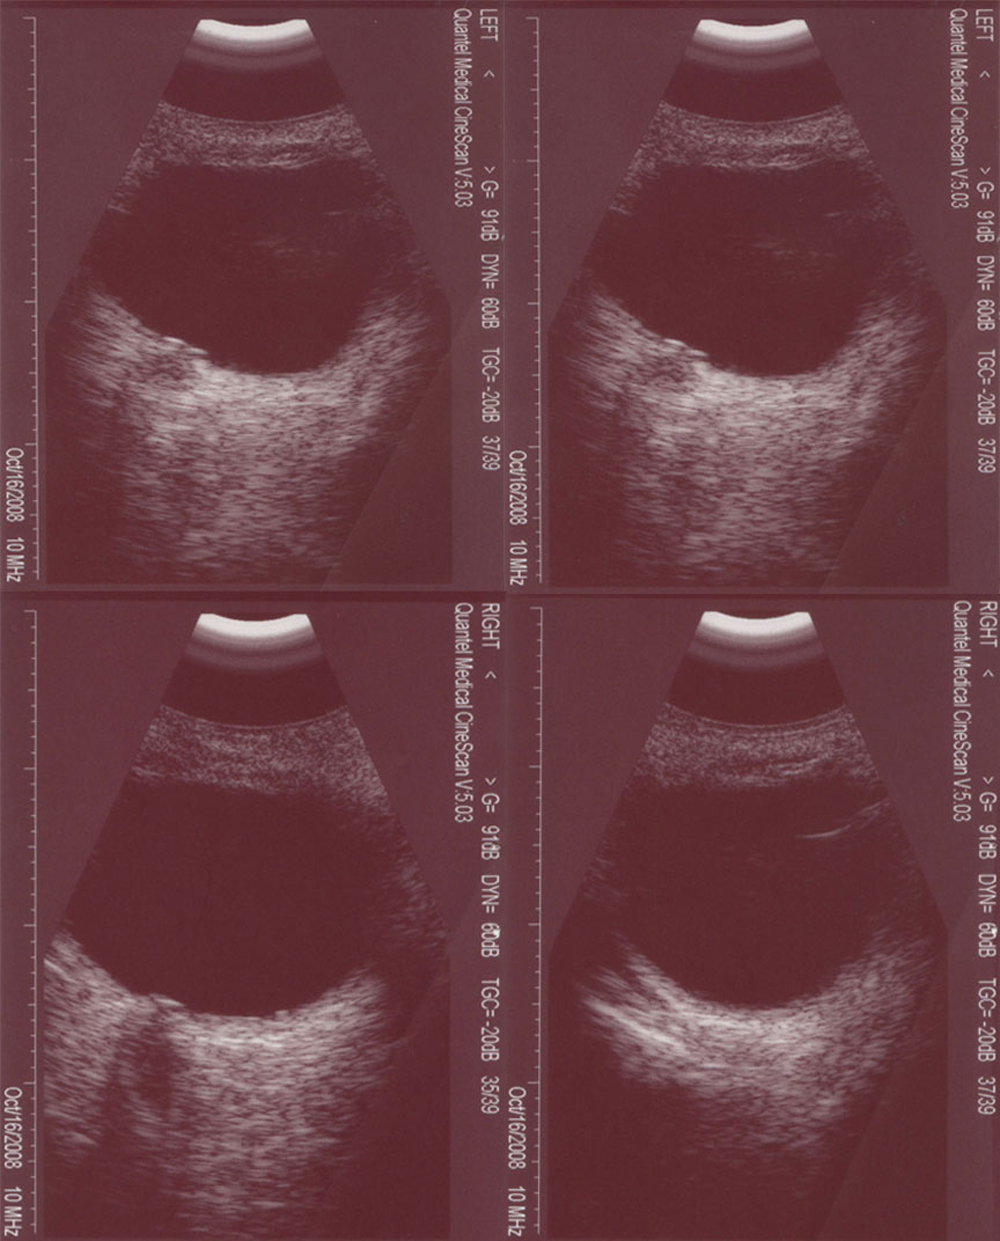

Figure 7 of Jia, Mol Vis 2010; 16:676-681.

Figure 7. Ocular manifestations of B-scanning. B-scanning revealed the abnormal structure of the vitreous body and optic nerve.